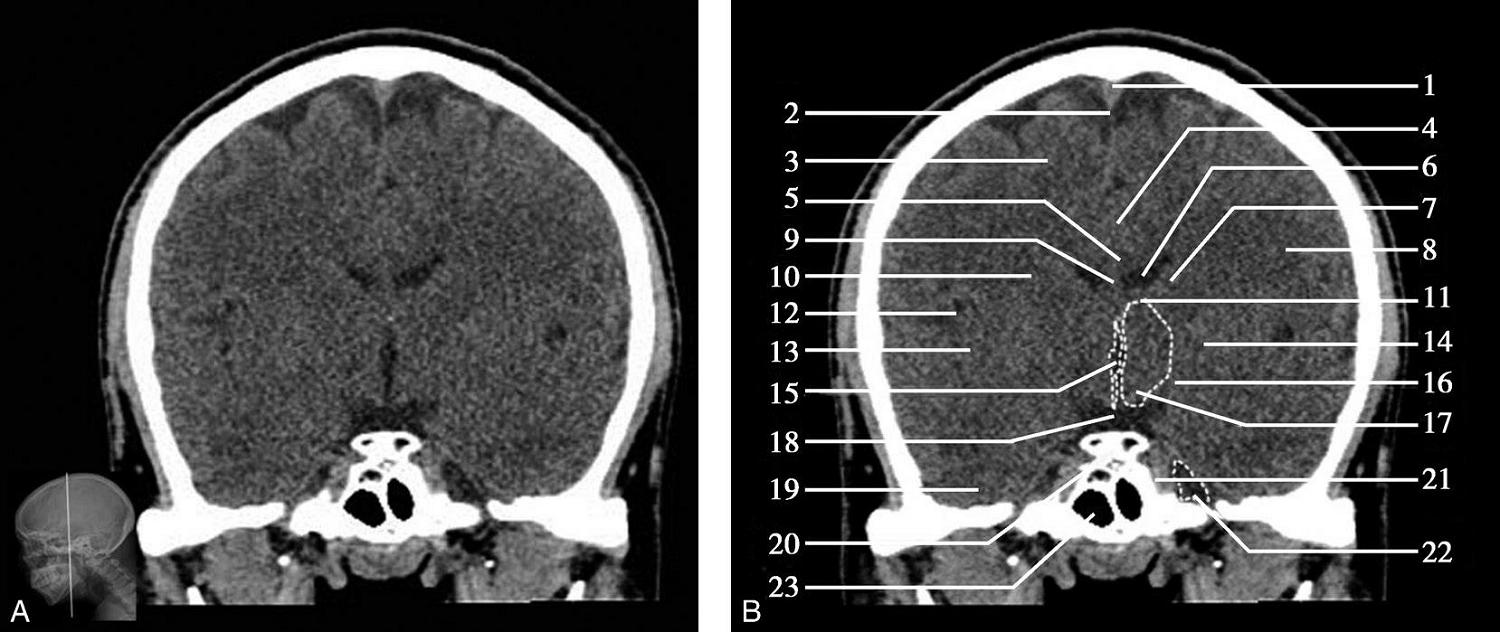

重要结构:视交叉、尾状核头、额叶、颞叶、外侧裂池(图1-2-52、图1-2-53)。

图1-2-52 视交叉层面

A.冠状面;B.冠状面标注

1.上矢状窦;2.大脑镰;3.额叶;4.扣带回;5.胼胝体体部;6.侧脑室前角;7.尾状核头部;8.内囊前肢;9.透明隔;10.豆状核;11.隔核;12.伏隔核;13.视交叉;14.鞍上池;15.外侧裂池;16.前床突;17.颞叶;18.海绵窦;19.蝶窦

图1-2-53 视交叉层面(骨窗)

1.矢状缝;2.顶骨;3.顶颞缝;4.前床突;5.颞骨;6.蝶鳞缝;7.蝶窦;8.颧弓;9.翼突内侧板;10.翼突外侧板

此层面正中线上部有大脑纵裂池及其内的大脑镰,大脑镰的上端与上矢状窦相连,下端毗邻胼胝体体部,胼胝体纤维连接双侧额叶。双侧额叶的外侧面,自上而下有额上回、额中回及额下回。胼胝体体部上方大脑镰的两侧有扣带回及扣带沟。胼胝体体部下方正中是透明隔,其两侧近似三角形为侧脑室前角,侧脑室前角顶壁为胼胝体,内侧壁上部为透明隔,底壁由隔核与伏隔核组成,外侧壁为尾状核头部。尾状核头外侧依次为内囊前肢、豆状核、外囊及屏状核。内囊位于尾状核头的外下方,是大脑皮质与皮质下中枢间的上下行纤维组成的投射纤维的主要通路。豆状核位于内囊的外下方,分为内侧的苍白球及外侧的壳核。胼胝体嘴部下方自上而下依次为大脑纵裂池、视交叉、鞍上池。视交叉两侧外下方为前床突的骨性断面,前床突内下方为海绵窦,其内可见颈内动脉断面,前床突外侧为两侧颞叶,两侧额叶与颞叶借外侧裂池分隔,额叶位于外侧裂池上方,颞叶位于外侧裂池下方。海绵窦下方中线区为蝶窦,蝶窦下方中部为鼻腔,鼻腔两侧为颞下窝。